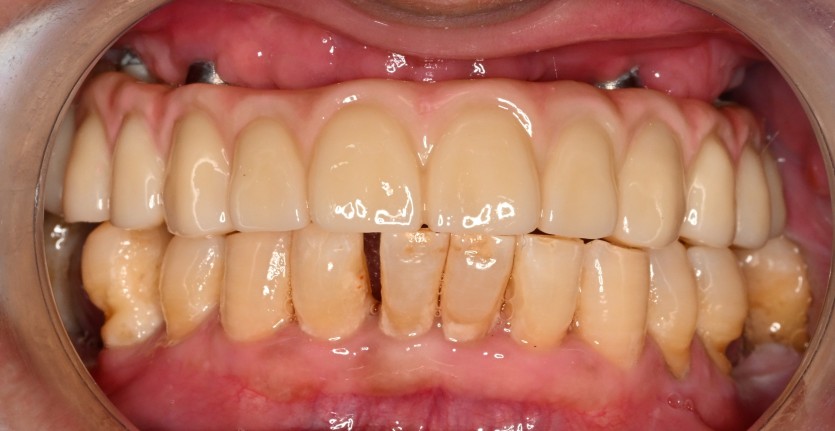

상악 풀아치 임플란트 증례입니다.

6개의 임플란트로 완성하였습니다.